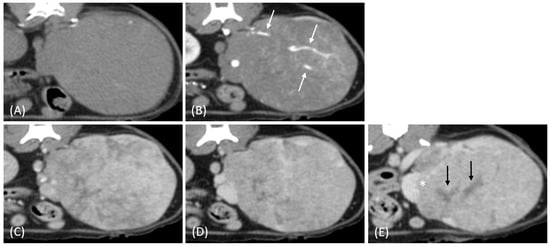

Figure 4.

(A) Pre-contrast, (B) corticomedullary phase, (C) nephrographic phase, and (D) delayed nephrographic/early excretory phase contrast-enhanced computed tomography (CT) images of a renal cell carcinoma. The tumors are bilateral, predominantly demonstrating an expansile growth pattern. They appear relatively homogeneous and hypoattenuating, resembling the imaging characteristics of multiple lymphoma masses. Progressive enhancement is observed throughout the phases. These findings highlight the overlapping imaging features between renal cell carcinoma (RCC) and lymphoma in certain cases.